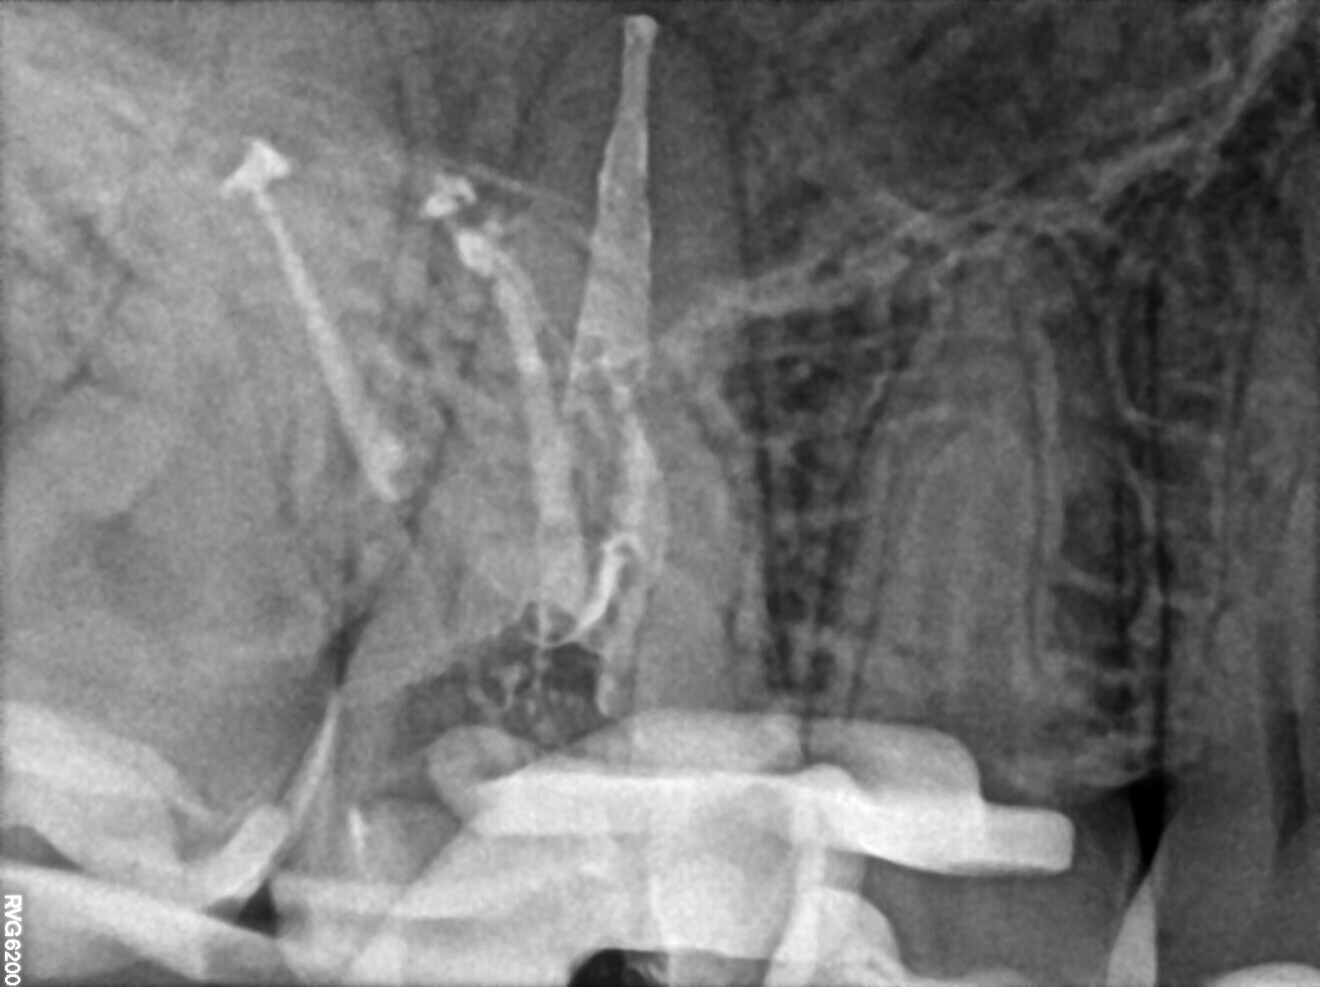

Figs. 1a–c. (All images: Bartłomiej Karaś and Grzegorz Witkowski)

A 28-year-old female patient was referred to Dr Karaś’s office because the previous dentist was not able to locate the orifice of the second mesiobuccal (MB2) canal in tooth #16. Owing to her medical history, endodontic treatment was performed, the tooth being symptomatic. A CBCT scan was performed in order to examine the mesial root and create a treatment plan. The shape of the root and the widening of the periodontal ligament indicated a separate path and apical foramen of an MB2 canal. Also, the slice showing the palatal part of the MB root revealed a small path, suggesting the presence of an MB2 canal. There were also visible signs of inflammation around the apices of the MB and distobuccal (DB) root and in the membrane of the maxillary sinus (Fig. 1).